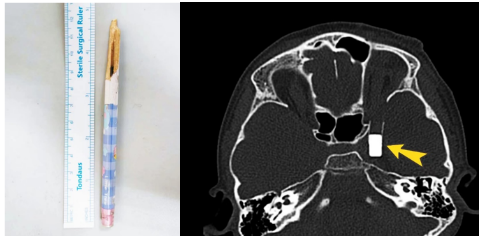

左图:患者自行拔出的铅笔残端。右图:术前评估异物位置。

经过眼科、介入血管外科、儿科、麻醉科等专家们的初步评估,小古丽的伤情渐渐明晰起来:铅笔木制主体已经自行拔出,异物位于中颅窝底部临近海绵窦的部位,最尾端位于眶上裂的后方。幸运的是,橡皮头没有戳破大动脉。眼眶内仅有微小残端保留一线手术机会。